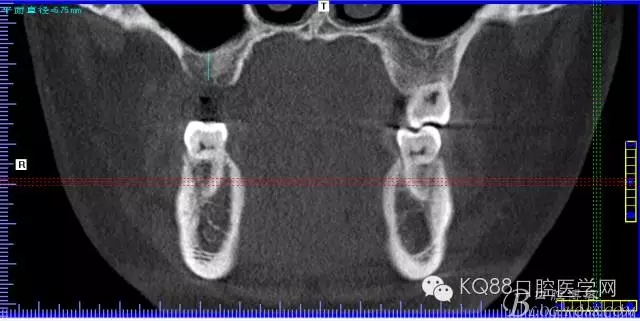

下面是拔牙前 CBCT

清晰可見根尖部陰影區(qū)域明顯。遠中頰根

近中頰跟,同時可以看出離上頜竇比較近,且伴有骨缺損。

這個切面可以看到根裂。